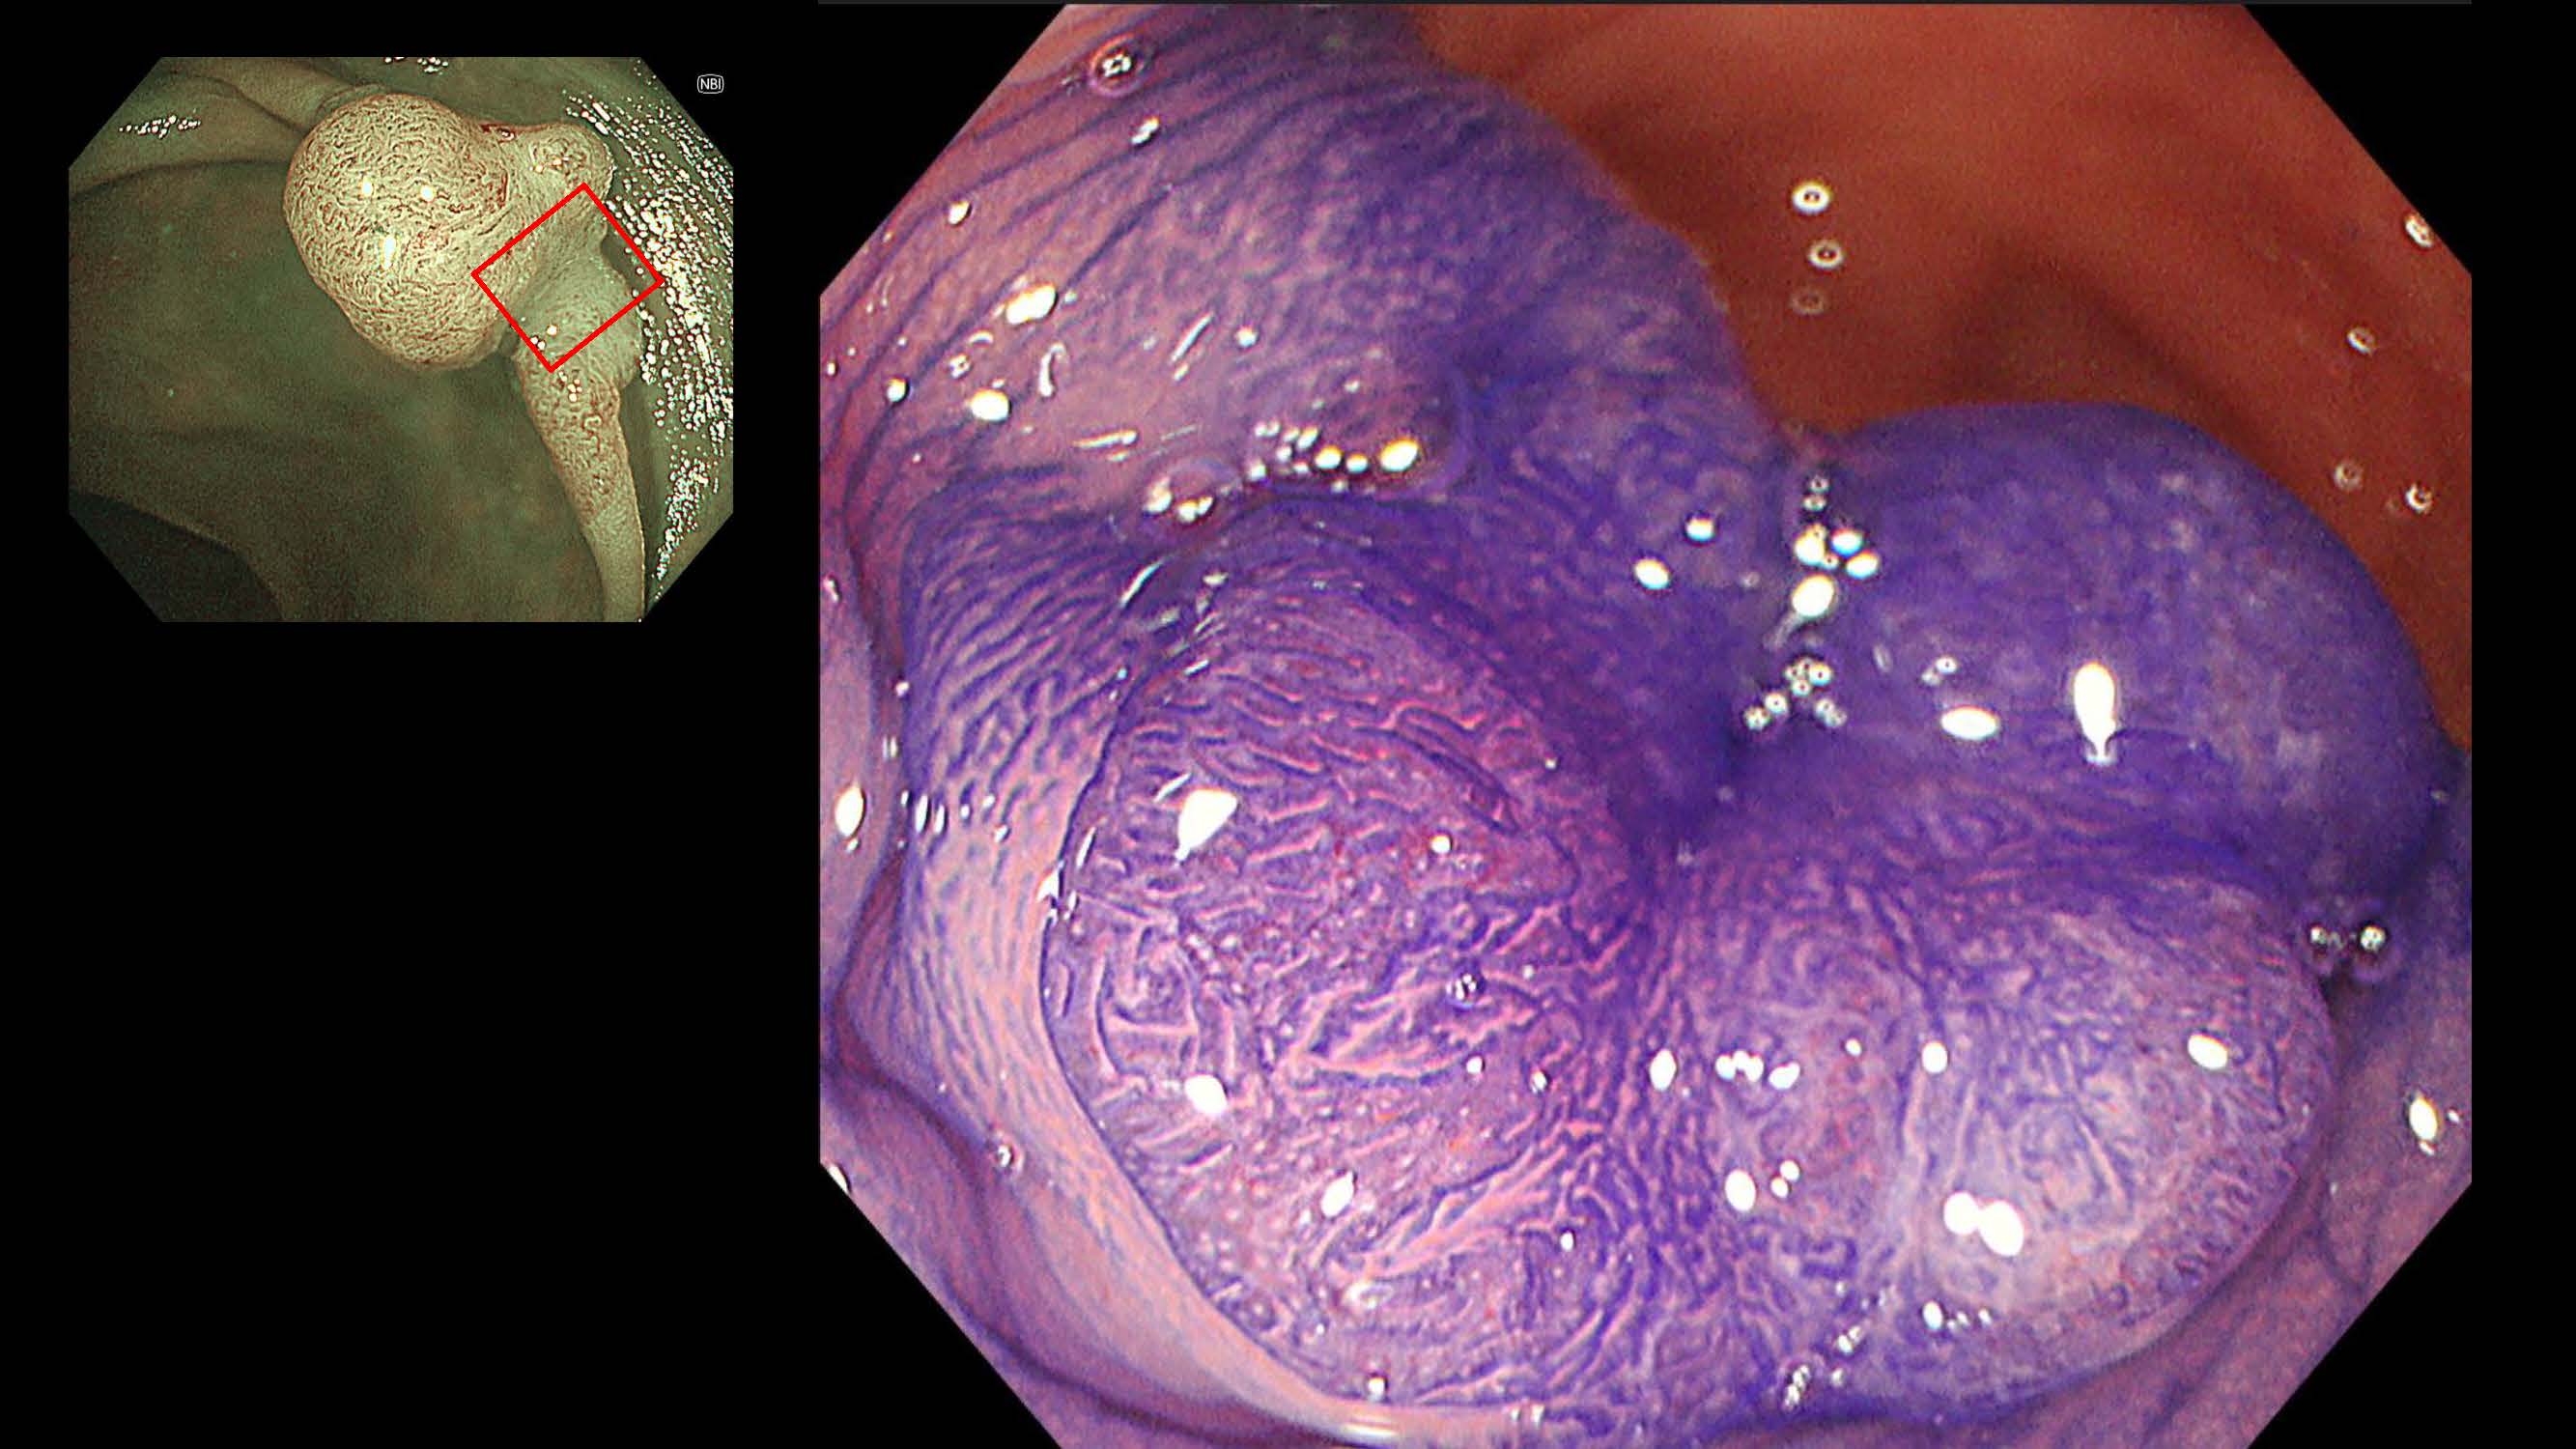

消化管Mapping~大腸~ 2025.6.11

消化管Mapping~大腸~

消化器内科

内視鏡検査・治療

消化管Mapping